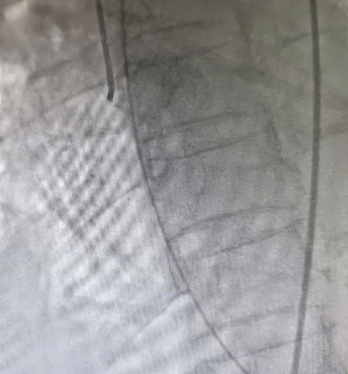

![]() |

| Hình ảnh hệ động mạch vành không thấy hẹp tắc - Ảnh BVCC |

Mặc dù chụp mạch vành không phát hiện tổn thương tắc nghẽn, các bác sĩ tiếp tục quyết định chụp hình ảnh buồng tim. Kết quả cho thấy rối loạn vận động điển hình của hội chứng Takotsubo, với tăng co bóp ở đáy và giảm vận động ở mỏm tim, xác định đây là bệnh cơ tim cấp do căng thẳng.